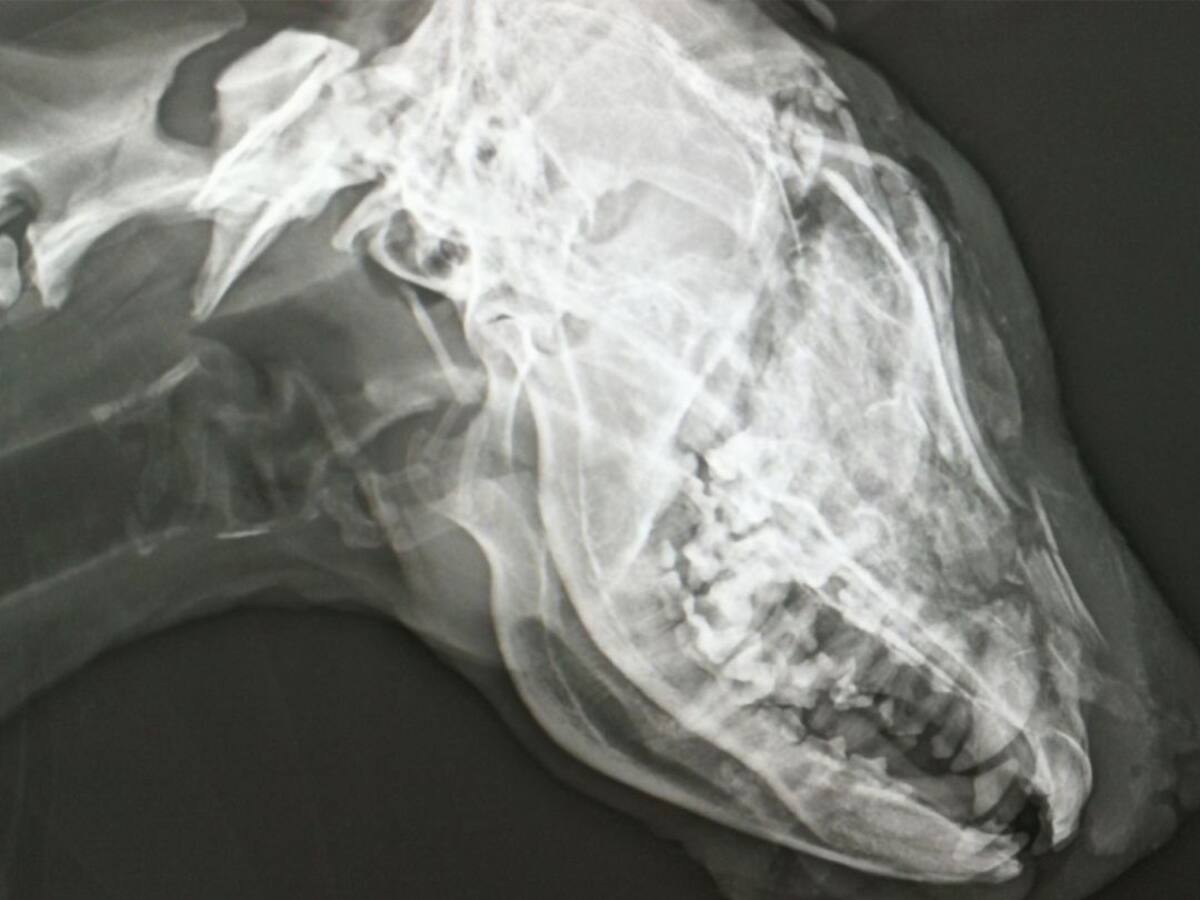

El ayuntamiento de Socuéllamos recuerda, en San Antón, su campaña contra el abandono y el maltrato animal

Esta lleva por título "Ante el abandono de animales, ¡sé responsable! Es la única garantía".